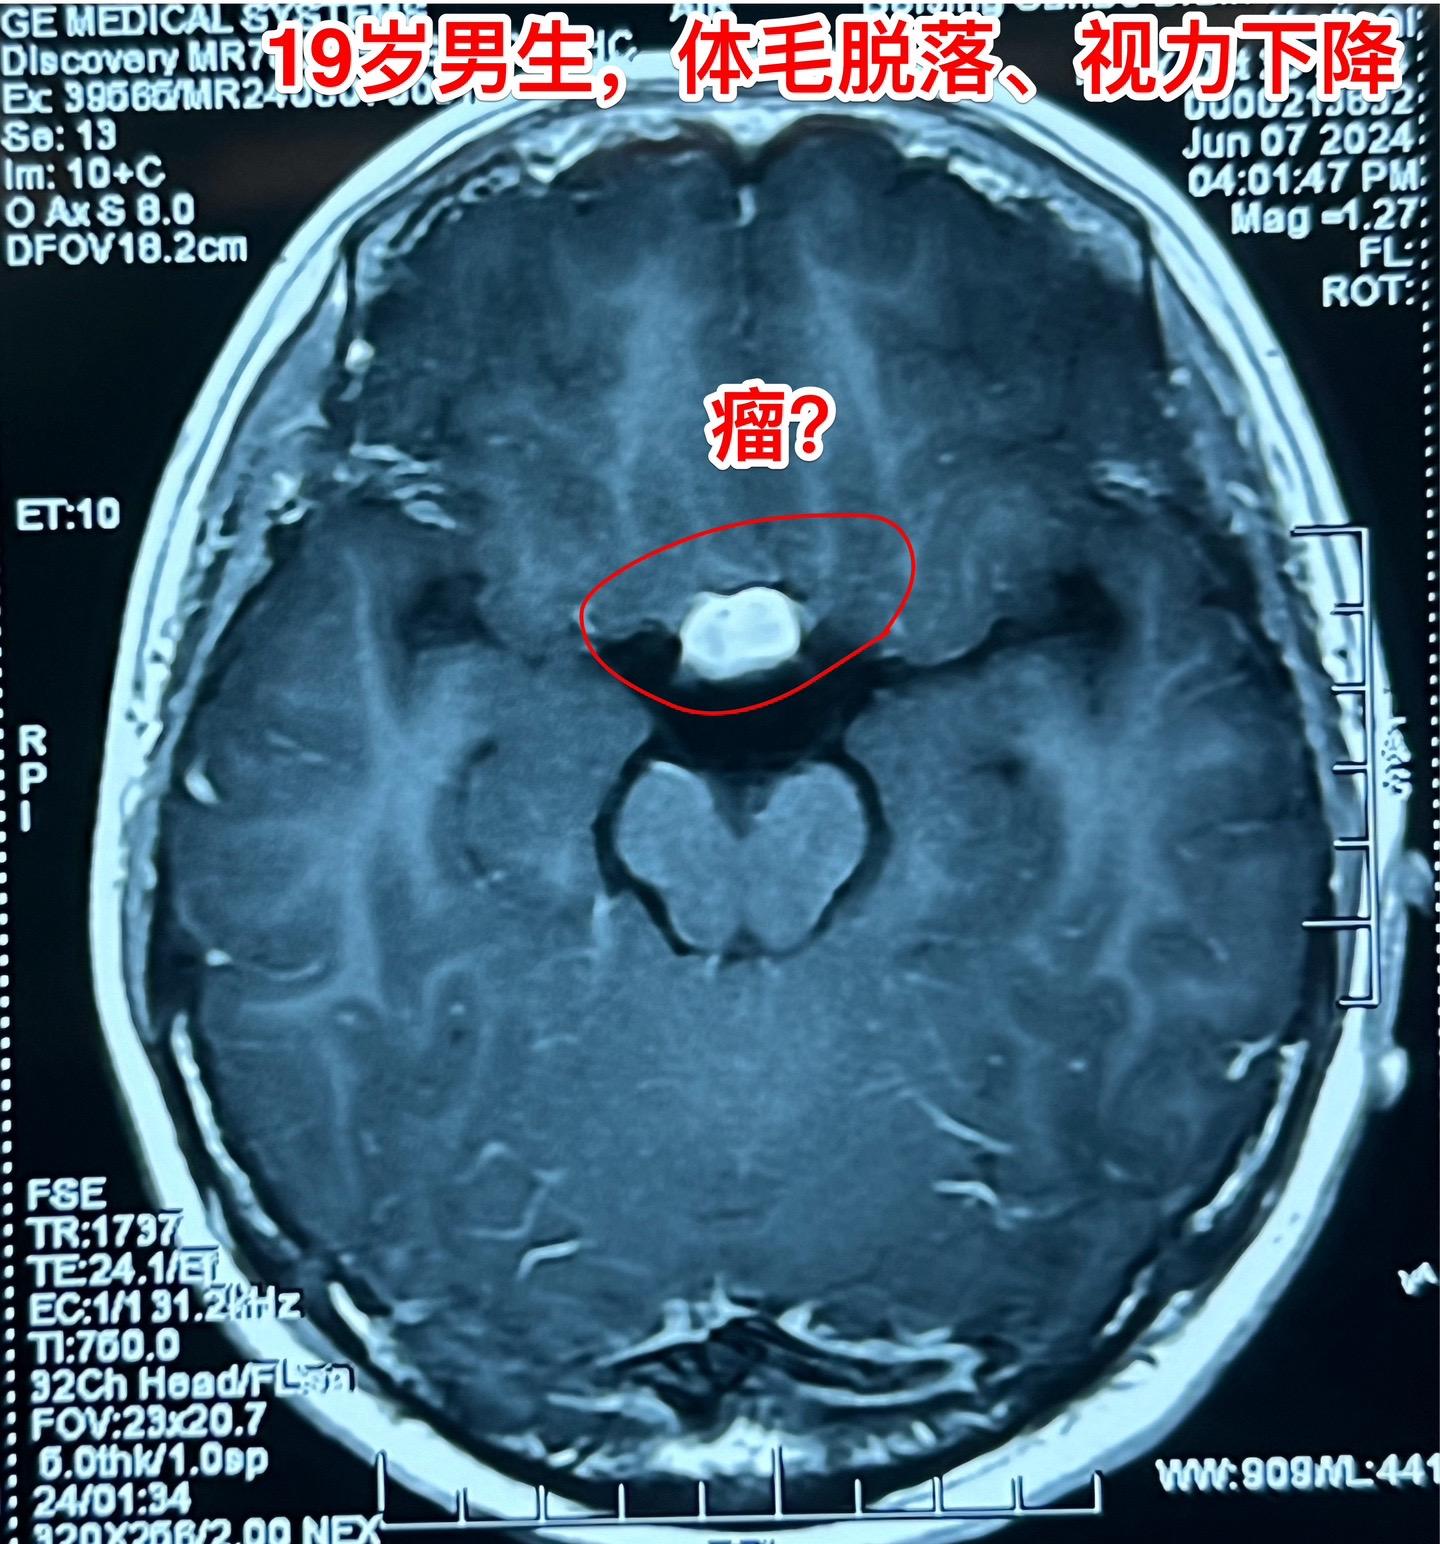

19岁重庆市的大学生发现自己体毛脱落!19岁重庆市的大学男生,发现自己体毛脱落,毫无阳刚之气,视力下降,到医院去化验发现雄激素几乎为零了。最近渐渐地还出现多饮多尿,以前夜间不上厕所的,现在夜间排尿2-3次。 到医院去检查磁共振发现鞍区病变,怀疑是颅咽管瘤或者是生殖细胞瘤,遂到北京来就医。 6月13日作了肿瘤活检术,术中两次的快速冰冻病理报告均是生殖细胞瘤。后期可以作化疗+小剂量放疗,有望获得好的预后!